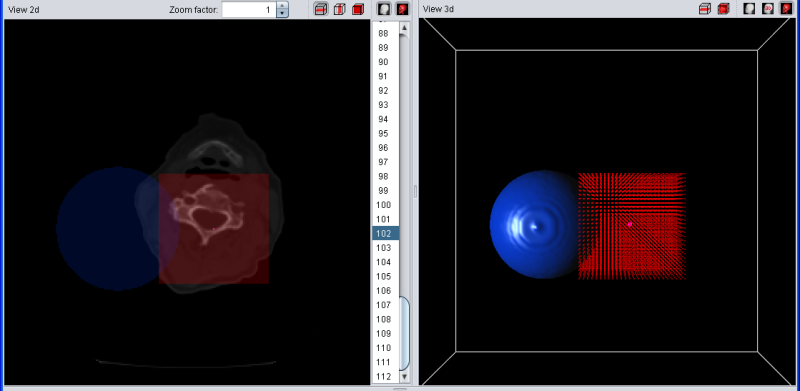

The temporary selection is always drawn in red. For example, if you have a blue segment wich overlaps with the current selection, the overlapping region will be drawn in purple since red + blue = purple. To make things easier to see, a simple geometric shaped blue segment is used (sphere) and the temorary segment/selection is shaped like a small red box.

|

| Selection (red) and segment (blue) |